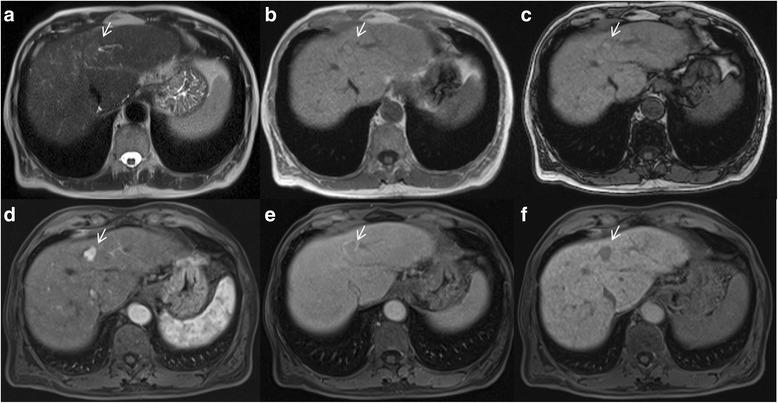

Liver Imaging Reporting and Data System (LI-RADS) is a system for interpreting and reporting of imaging features on multidetector computed tomography (MDCT) and magnetic resonance (MR) studies in patients at risk for hepatocellular carcinoma (HCC). American College of Radiology (ACR) sustained the spread of LI-RADS to homogenizing the interpreting and reporting data of HCC patients. Diagnosis of HCC is due to the presence of major imaging features. Major features are imaging data used to categorize LI-RADS-3, LI-RADS-4, and LI-RADS-5 and include arterial-phase hyperenhancement, tumor diameter, washout appearance, capsule appearance and threshold growth. Ancillary are features that can be used to modify the LI-RADS classification. Ancillary features supporting malignancy (diffusion restriction, moderate T2 hyperintensity, T1 hypointensity on hapatospecifc phase) can be used to upgrade category by one or more categories, but not beyond LI-RADS-4. Our purpose is reporting an overview and update of major and ancillary MR imaging features in assessment of HCC.

肝脏影像报告和数据系统(LI-RADS)是一种用于解读和报告肝细胞癌(HCC)高危患者多排螺旋计算机断层扫描(MDCT)和磁共振成像(MR)检查影像特征的系统。美国放射学会(ACR)推动了LI-RADS的推广,以统一HCC患者的解读和报告数据。HCC的诊断基于主要影像特征的存在。主要特征是用于对LI-RADS-3、LI-RADS-4和LI-RADS-5进行分类的影像数据,包括动脉期强化、肿瘤直径、廓清表现、包膜表现和阈值生长。辅助特征可用于修改LI-RADS分类。支持恶性的辅助特征(扩散受限、T2中等度高信号、肝胆期T1低信号)可用于将类别提升一级或多级,但不超过LI-RADS-4。我们的目的是报告在HCC评估中主要和辅助MR成像特征的概述及更新情况。